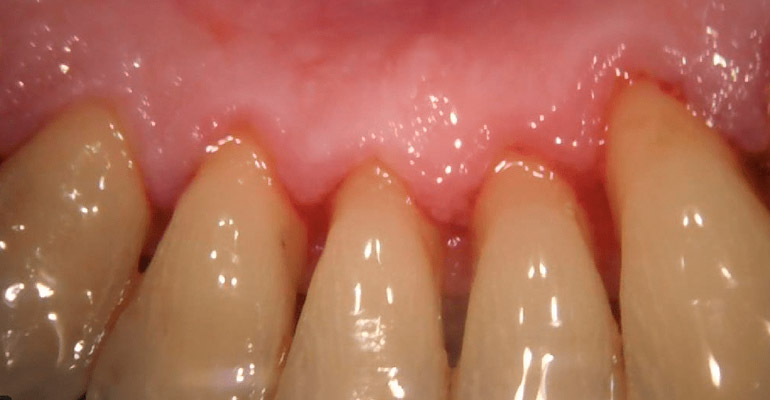

PERIODONCIA

CASOS CLÍNICOS

A continuación puede visualizar algunos clasos clínicos realizados en nuestra clínica, podrá informarse sobre el tratamiento realizado y visualizar las imágenes reales antes y después de nuestro tratamiento.

Todas las imágenes son de pacientes reales, algunas imágenes pueden herir su sensibilidad.

Pulse sobre las pestañas superiores para visualizar los diferentes casos clínicos.

Paciente periodontal con caries incipientes radiculares y desgaste oclusal por bruxismo.

Se realizo una rehabilitación con coronas para restablecer dimensión vertical y estética.